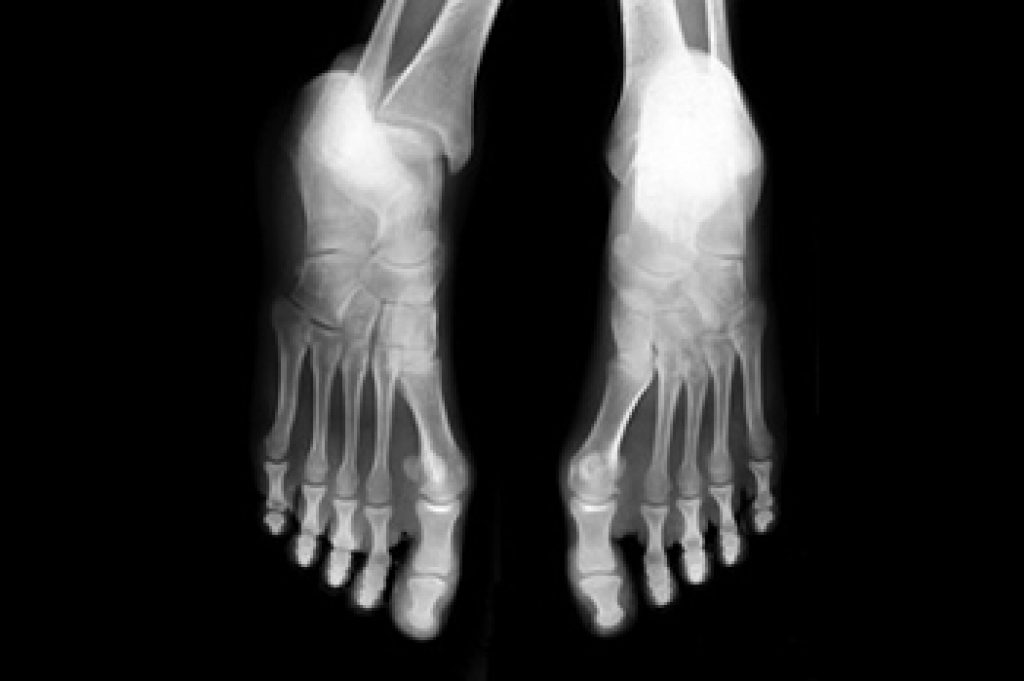

Podiatric biomechanics is a particular sector of specialty podiatry with licensed practitioners who are trained to diagnose and treat conditions affecting the foot, ankle and lower leg. Biomechanics deals with the forces that act against the body, causing an interference with the biological structures. It focuses on the movement of the ankle, the foot and the forces that interact with them.